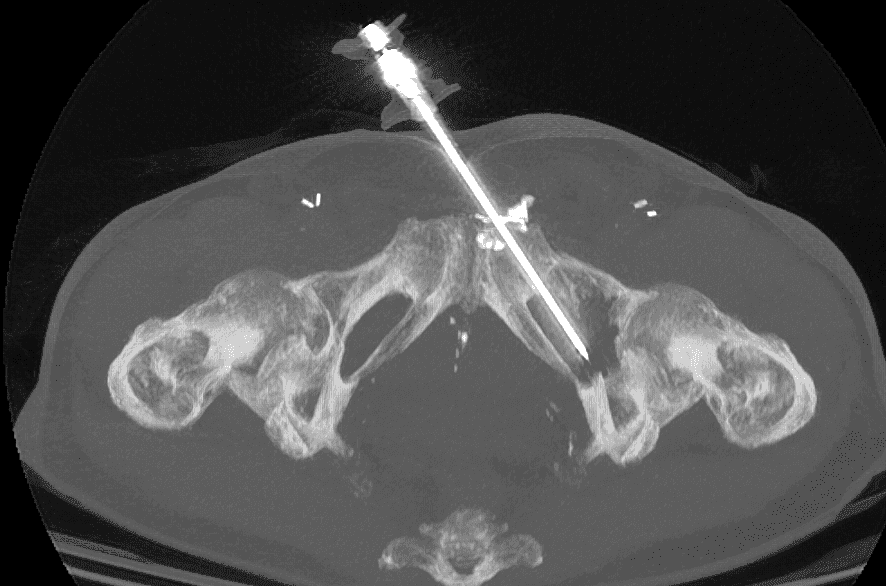

Insertion et déploiement du matériel d’ostéosynthèse :

Une fois l’aiguille positionnée, le vissage est réalisé en respectant la trajectoire prédéfinie, permettant de réaligner les fragments osseux.

Le vissage est ensuite fixé de manière à assurer une stabilité mécanique suffisante pour supporter les contraintes de la zone cotyloïdienne.

Un contrôle scanner final permet de vérifier la position du vissage et la qualité de la réduction anatomique, garantissant ainsi le succès de l’intervention.